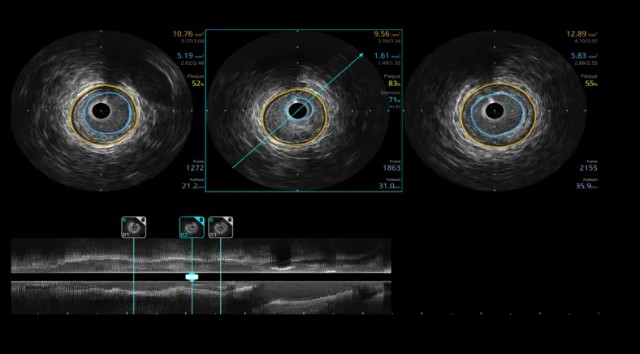

搭载最新一键定量的智能化工具

开立IVUS采用了业界领先的一键式自动解决方案,一键可自动精确识别测量血管,自动给出斑块负荷、面积狭窄率指标,更好辅助医生决策,缩短手术时间。

开立超声怎么导出图像步入冠脉精准化时代:开立高清IVUS获批上市_https://www.jmylbn.com_新闻资讯_第3张